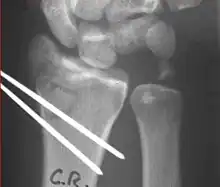

Surgical options have been shown to be successful in patients with unstable extra-articular or minimal articular distal radius fractures. These options include percutaneous pinning, external fixation, and ORIF using plating. Patients with low functional demand of their wrists can be treated successfully with nonsurgical management; however, in more active and fit patients with fractures that are reducible by closed means, nonbridging external fixation is preferred, as it has less serious complications when compared to other surgical options.[4] The most common complication associated with nonbridging external fixation is pin tract infection, which can be managed with antibiotics and frequent dressing changes, and rarely results in reoperation.[4] The external fixator is placed for 5 to 6 weeks and can be removed in an outpatient setting.[4]

Displaced intra-articular fractures

These fractures, although less common, often require surgery in active, healthy patients to address displacement of both the joint and the metaphysis. The two mainstays of treatment are bridging external fixation or ORIF. If reduction can be achieved by closed/percutaneous reduction, then open reduction can generally be avoided. Percutaneous pinning is preferred to plating due to similar clinical and radiological outcomes, as well as lower costs, when compared to plating, despite increased risk of superficial infections.[21] Level of joint restoration, as opposed to surgical technique, has been found to be a better indicator of functional outcomes.[4]